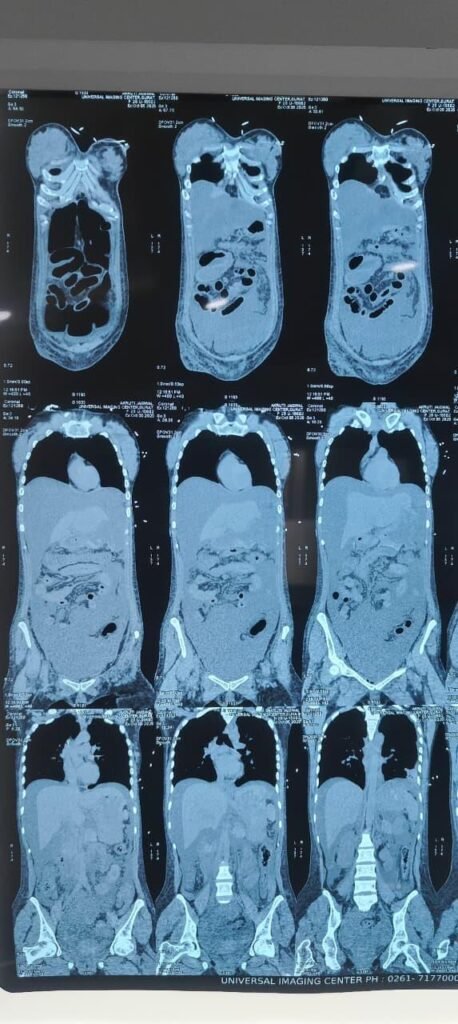

8) Imaging

CT Abdomen (5 Oct 2025, Universal Hospital)

Ill-defined, sloughed stomach wall, mainly fundus → perforation suspected.

Pneumoperitoneum, severe ascites, mesenteric haziness.

Long-segment edema in proximal small bowel + mild colonic wall thickening.

Moderate bilateral pleural effusion with basal collapse.

Generalized anasarca.

Impression: Severe corrosive gastritis with fundic necrosis ± perforation.

Vitals : BP 98/60, HR 110, SpO₂ 96% FiO₂ 40%, Temp 99.5°FUrine output : 30 mL/h (Improving)ABG : pH 7.28 / HCO₃⁻ 18 / pCO₂ 32Labs : Cr 1.5 mg/dL, WBC 15 000CT Abdomen (Plain – Reported 5 Oct 2025):

Stomach wall ill-defined and sloughed off (mainly fundus & greater curvature) → suggestive of perforation / gangrenous gastritis

Severe ascites with pneumo-peritoneum

Left > Right pleural effusion with basal collapse

Long segment edematous small bowel wall thickening, mild colonic thickening, generalized anasarca

Interpretation :

Severe corrosive gastric necrosis with perforation and peritonitis → Surgical intervention required.